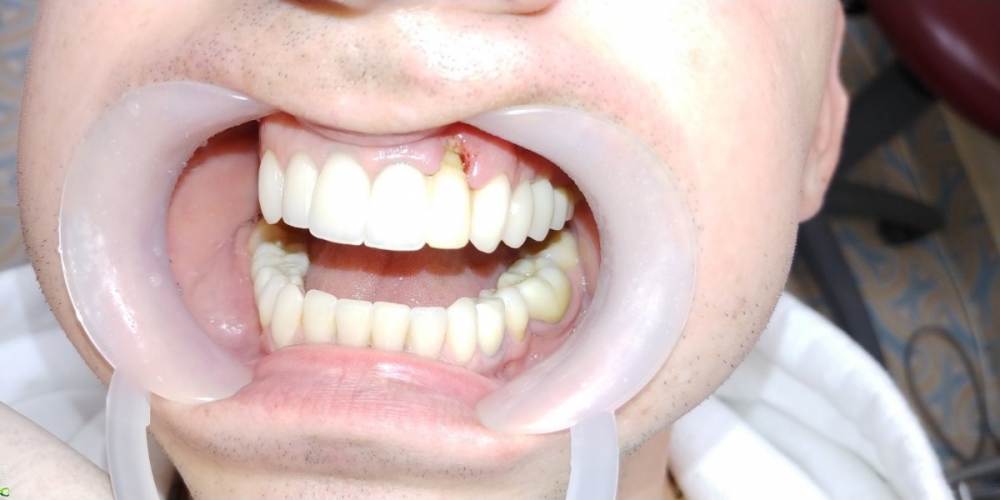

maksimstom Опубликовано 1 сентября, 2021 Автор Поделиться Опубликовано 1 сентября, 2021 Всем спасибо! Результат через 6 мес, 2 пластики десны 4 1 3 Ссылка на комментарий

Irouil Опубликовано 1 сентября, 2021 Поделиться Опубликовано 1 сентября, 2021 Как решили? учитывая исходник - очень внушительно! Ссылка на комментарий

maksimstom Опубликовано 2 сентября, 2021 Автор Поделиться Опубликовано 2 сентября, 2021 Тоннельно 1 транспл окклюзионно, 1 вестибулярно, ждал месяца 4, бугор подрос 1 Ссылка на комментарий